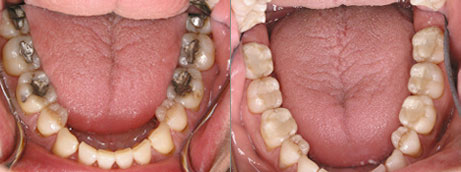

In the past, replacing big ugly silver fillings consisted of lab fabricated restorations. This would entail excessive tooth removal, impressions, temporaries, and two appointments. Now, by combining oldstyle care withnew age technology, we can save teeth, remove these mercury fillings and fix the broken down teeth in just one appointment.

photo of teeth with inlays and onlays